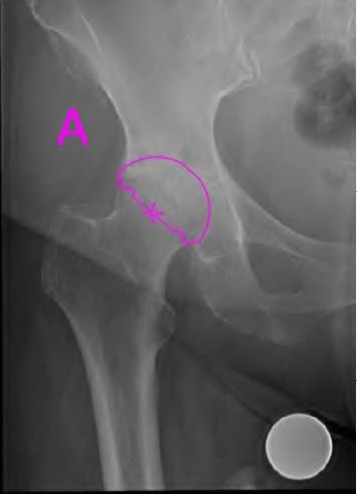

An 82-year-old woman falls and sustains the fracture shown in figure A. She denies any history of dislocation or prodromal pain prior to her fall. What is the most appropriate treatment?

The radiograph demonstrates a periprosthetic femur fracture extending to the tip of the stem. The long spiral fracture is consistent with a loose implant. The bone stock is sufficient. Therefore, this fracture pattern would classify as a B2 using the Vancouver classification system. The Vancouver classification for periprosthetic femoral fractures is simple yet incorporates all the pertinent factors such a location, stem fixation, and bone stock. Type A is a trochanteric fracture- lesser or greater. These can be treated non-operatively usually and ORIF if symptomatic. Type B fractures are around or just below the stem and are subdivided into three types. Type B1 is a fracture with a well fixed stem.

The treatment is cable plating or allograft struts or a combination of the two. Type B2 is a fracture with a loose stem with good bone stock. The treatment is a cementless porous coated long stem atleast two diameter length past the

fracture site. Type B3 is a fracture with a loose stem and comminution. For younger patients, use cementless porous coated long stems with allograft struts. For older patients, consider a tumor prosthesis. Cement fixation is sometimes necessary Type C is a fracture well below the stem tip. These can be treated independently of the prosthesis.

Springer et al showed optimal outcomes with revision involving long extensively-coated femoral stems for Vancouver B fractures.

Masri et al review the classification and treatment of periprosthetic femur fractures.